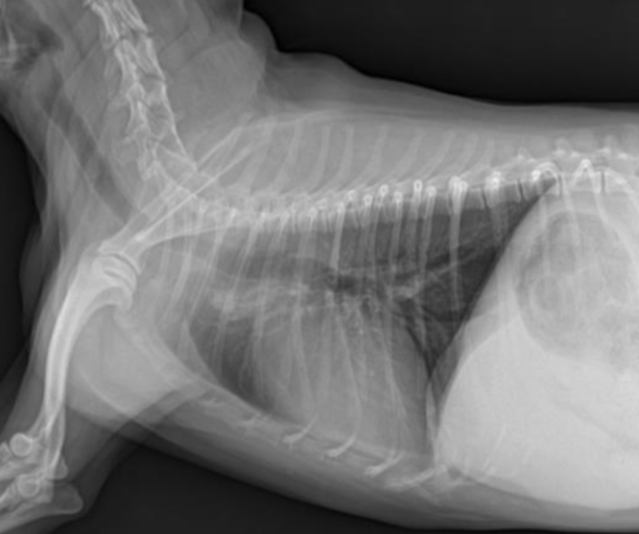

| RL (Right Lateral) | LL (Left Lateral) |

|---|---|

![]() | ![]() |

| 더 oval함. | 심장이 더 둥글게 보임(round). |

| 디테일한 심장 관찰에 좋음. | 폐혈관 촬영에 좋음. |